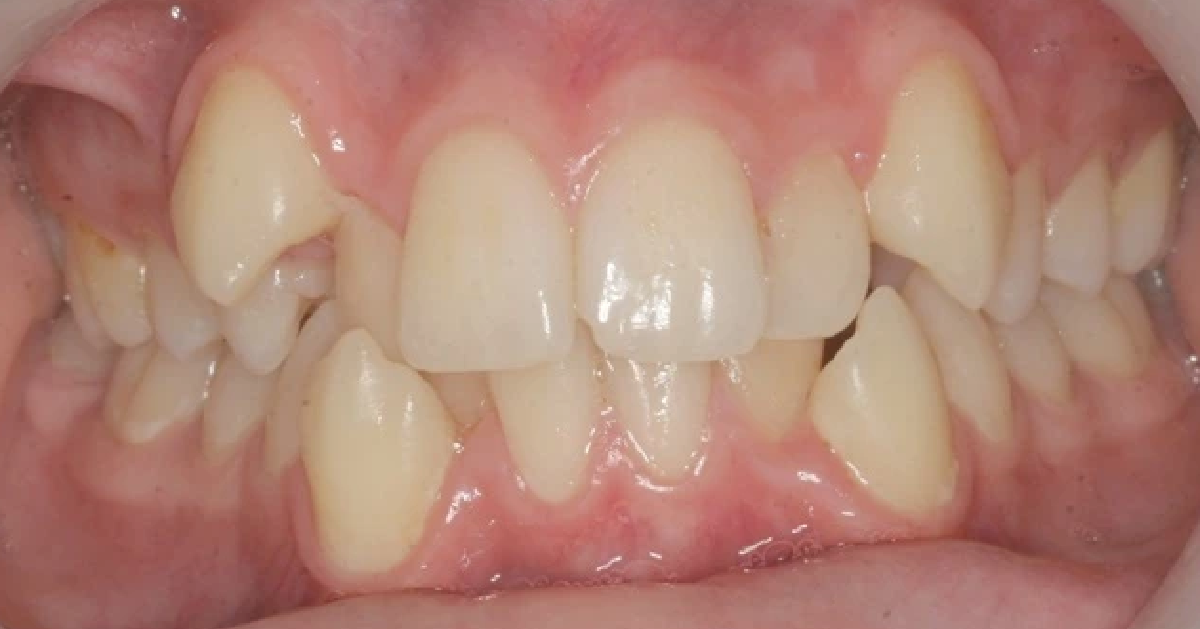

Hvorfor regulering kan være aktuelt

Hos Signe Storesund AS vurderes tannstilling og bitt for å se om det er behov for korrigering. Regulering kan være aktuelt ved bittfeil, trangstilling eller andre forhold som påvirker funksjon, utvikling eller tannstilling. Det tas stilling til om behandling er nødvendig, og når den eventuelt bør starte.